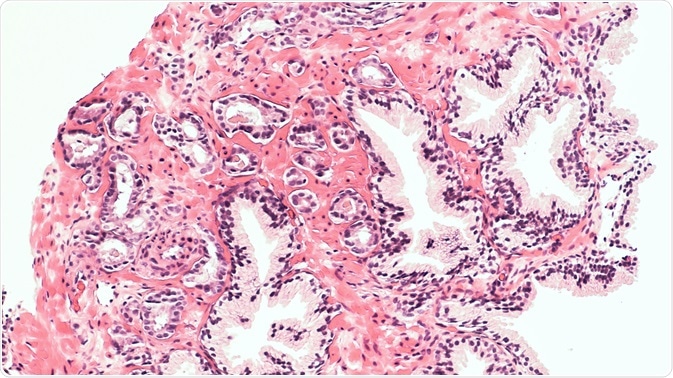

Shutterstock | David Litman

This experiment intends to measure how well digital image analysis correlates with pathologist visual scoring by a semi-quantitative scoring technique, as well as their reproducibility and how the former method matches up with disease-specific survival statistics. The method involved the use of a large PCa tissue microarrays (TMA) slides stained for ERβ2.

Prostate cancer TMAs were subjected to digital imaging and then the images were scored either visually or by digital analysis for ERβ2 staining in the tumor epithelium. The images for visual scoring were created by scanning the stained slides using an automated Tissuefax microscope (TissueGnostics, Tarzana, CA) and then were reviewed with the help of an online web gallery.

The ERβ2 staining was scored according to the individual TMA spots by a pathologist who had been blinded to the clinical features. The images were analyzed twice independently to assess the reproducibility of visual scoring. The image analysis data was then analyzed further to look for any significant association with the recurrence-free survival period as well as the disease-specific survival after radical prostatectomy.